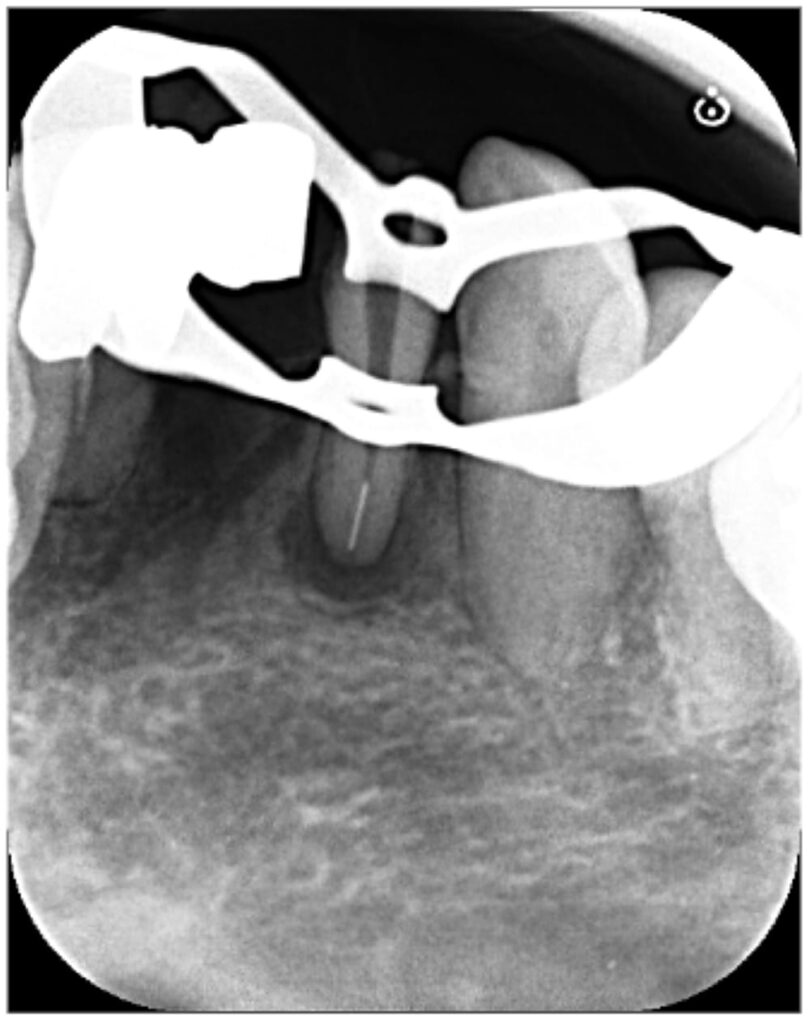

初診来院時の状態

下顎前歯の根の先に、はっきりと黒い影(骨吸収像)が認められます。腫れや痛みの症状もあることから、根尖性歯周炎と診断しました。

レントゲン画像では、根管内に白い不透過像も認められ、形状からおそらく破折ファイルと推測される状態でした。

元々装着されていたブリッジを切断して除去し、ラバーダム装着後、まずは根管上部のガッタパーチャ(根の中の詰め物)を除去しました(レントゲン写真はガッタパーチャ除去直後)。